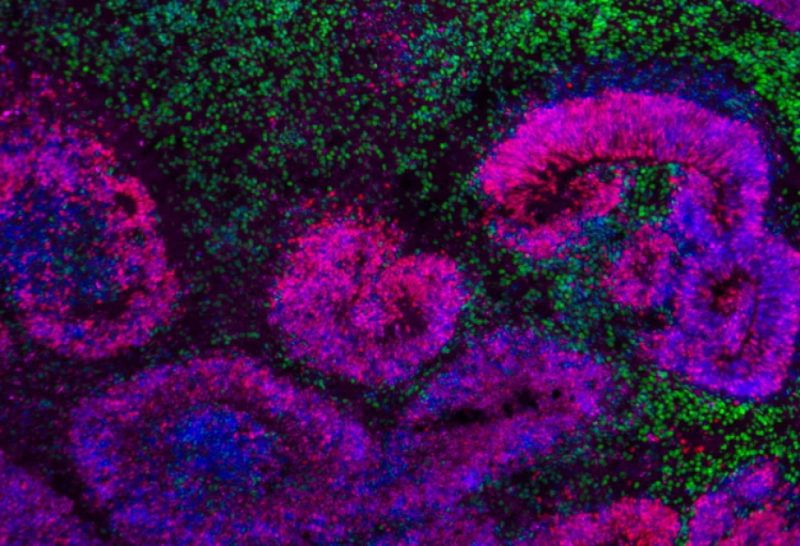

AZƏRTAC “Reuters” agentliyinə istinadla xəbər verir ki, tədqiqatçılar inkişaf edən insan və məməli heyvan beyninin atlaslarının ilk layihəsini tamamladıqlarını bildiriblər. Tədqiqat insan və siçanın beyin hüceyrələrinə yönəlib, meymunun beyin hüceyrələrində də bəzi işlər aparılıb. Alimlər ilkin layihələrində müxtəlif növ beyin hüceyrələrinin inkişafını xəritələşdirib, onların necə doğulduğunu, fərqləndiyini və unikal funksiyalara malik müxtəlif növlərə necə çevrildiyini izləyiblər. Həmçinin onlar zamanla bu hüceyrələrdə genlərin necə açıldığını və ya söndürüldüyünü də öyrəniblər.

Alimlər beyin proseslərini idarə edən əsas genləri müəyyən edib, insan və heyvan beyinləri arasında hüceyrələrin inkişafının bəzi ortaq cəhətlərini, eləcə də əvvəllər məlum olmayan hüceyrə növlərini müəyyən ediblər. Beləliklə, insan beyninin bəzi unikal aspektləri aşkar edilib.

Tədqiqatçılar siçan beynində 5 mindən çox hüceyrə növü aşkar ediblər. İnsan beynində ən azı bir o qədər hüceyrə növü olduğu düşünülür. “İnkişaf edən beyin inanılmaz dərəcədə sirli bir quruluşdur, çünki ona daxil olmaq çətindir, çoxlu fərqli hüceyrə növlərindən ibarətdir və sürətlə dəyişir. Beynin inkişafı zamanı baş verən ümumi mənzərə dəyişikliklərini bilsək də, indi bu atlas sayəsində həmin prosesləri daha ətraflı şəkildə anlayırıq”, – deyə tədqiqatın digər iştirakçısı, ABŞ nevroloqu Aparna Bhaduri bildirib.

Araşdırma göstərib ki, insanın beyin şişlərindəki hüceyrələrin bir alt qrupu embrional progenitora bənzəyir və bu, bu bədxassəli şişlərin yaranmasına səbəb olur. Tədqiqatçılar insan beyninin bəzi unikal aspektlərini müəyyən ediblər. Bir nümunə heyvanlarda daha sürətli inkişaf qrafiki ilə müqayisədə döldən yeniyetməliyə qədər insan beyninin uzun inkişaf dövrü səbəbindən kortikal hüceyrə növlərində uzunmüddətli differensiasiya prosesi ilə əlaqəlidir. Yeni müəyyən edilmiş beyin hüceyrə növləri arasında hərəkəti və bəzi digər funksiyaları idarə edən neokorteks və striatum bölgəsinə aid olanlar da var.